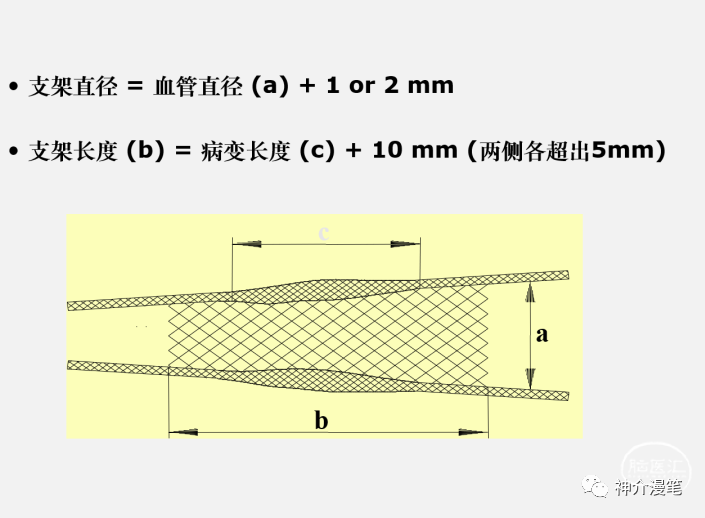

基于前面啰七八嗦的介绍,那么更适合不同支架的应用场景是什么样子的呢?声明一点的是纯学术探讨,没有任何不良导向和利益导向

关键词:开环,镍钛,快交,无锥形支架。另外PRICISE支架8以下可以使用6F导引导管进行释放,这在部分通路迂曲的血管条件下尤为重要。支架释放过程不需要推挤支架,只需要把住推送杆后等张力扒开支架即可。

Protege支架实际上在实际的使用过程中个人感觉和Pricise支架没有过多的区别。二者手感比较类似,区别点在于Protege有普通支架和锥形支架两种。

颈动脉支架其实大部分情况下都不是困难病例,很多兄弟的起手手术也是选择颈动脉支架术。但是能做并不一定代表会做,会做也不代表一定就能做好,根据病变的特点:偏心、钙化、斑块性质,血管走行的特点,远端形态等一系列的特点综合判断患者的整体情况。术前制定预期目标,罗列值得关注的问题,进而选择一个最理想的支架。其实大部分情况下,选择任何一个支架可能都是可行的,但是真正的了解了支架的特点后,在极端情况下,你的一个正确选择可能会改变手术的结果和病人的预后。就像邓主任说的:没有错误的支架,只有术者错误的选择。